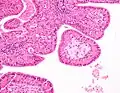

The appearance of this tumor under the microscope is unique. There are cystic spaces surrounded by two uniform rows of oncocytes, which are epithelial cells with abundant, granular, eosinophilic cytoplasm.[7] The cystic spaces have epithelium referred to as papillary infoldings that protrude into them. Additionally, the epithelium has lymphoid stroma with germinal center formation.

Intermediate magnification micrograph of a Warthin tumor. Intermediate magnification micrograph of a Warthin tumor.